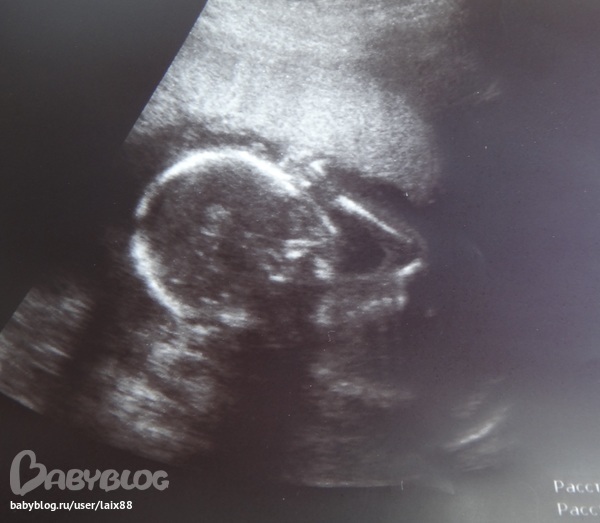

Малыш тостый, длиннорукий и длинноногий, опережает срок на неделю - по УЗИ 19 нед и 3 дня. БПР 43,9, вес плода 270 гр. Мужииик! :)))

На фото в позе мыслителя